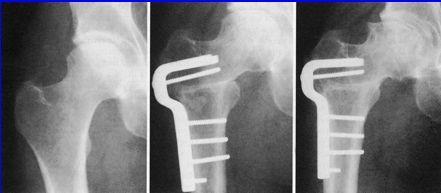

Osteotomías en valgus

Osteotomías en varus

Osteotomías